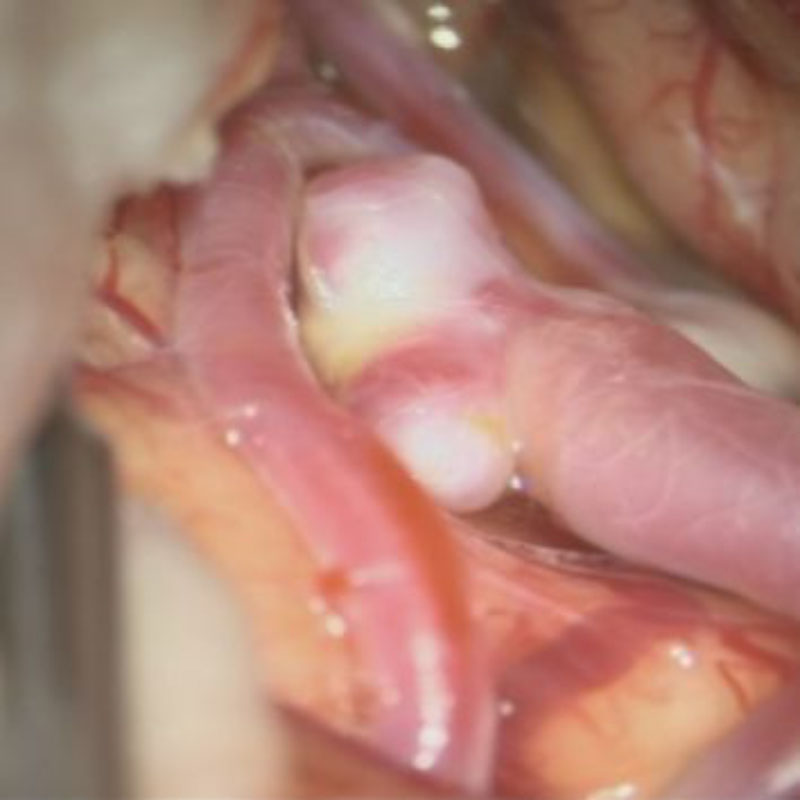

21

'26年4月

50代

左中大脳動脈瘤

クリッピング術

手術前

クリップ前

クリップ後

術後血管撮影